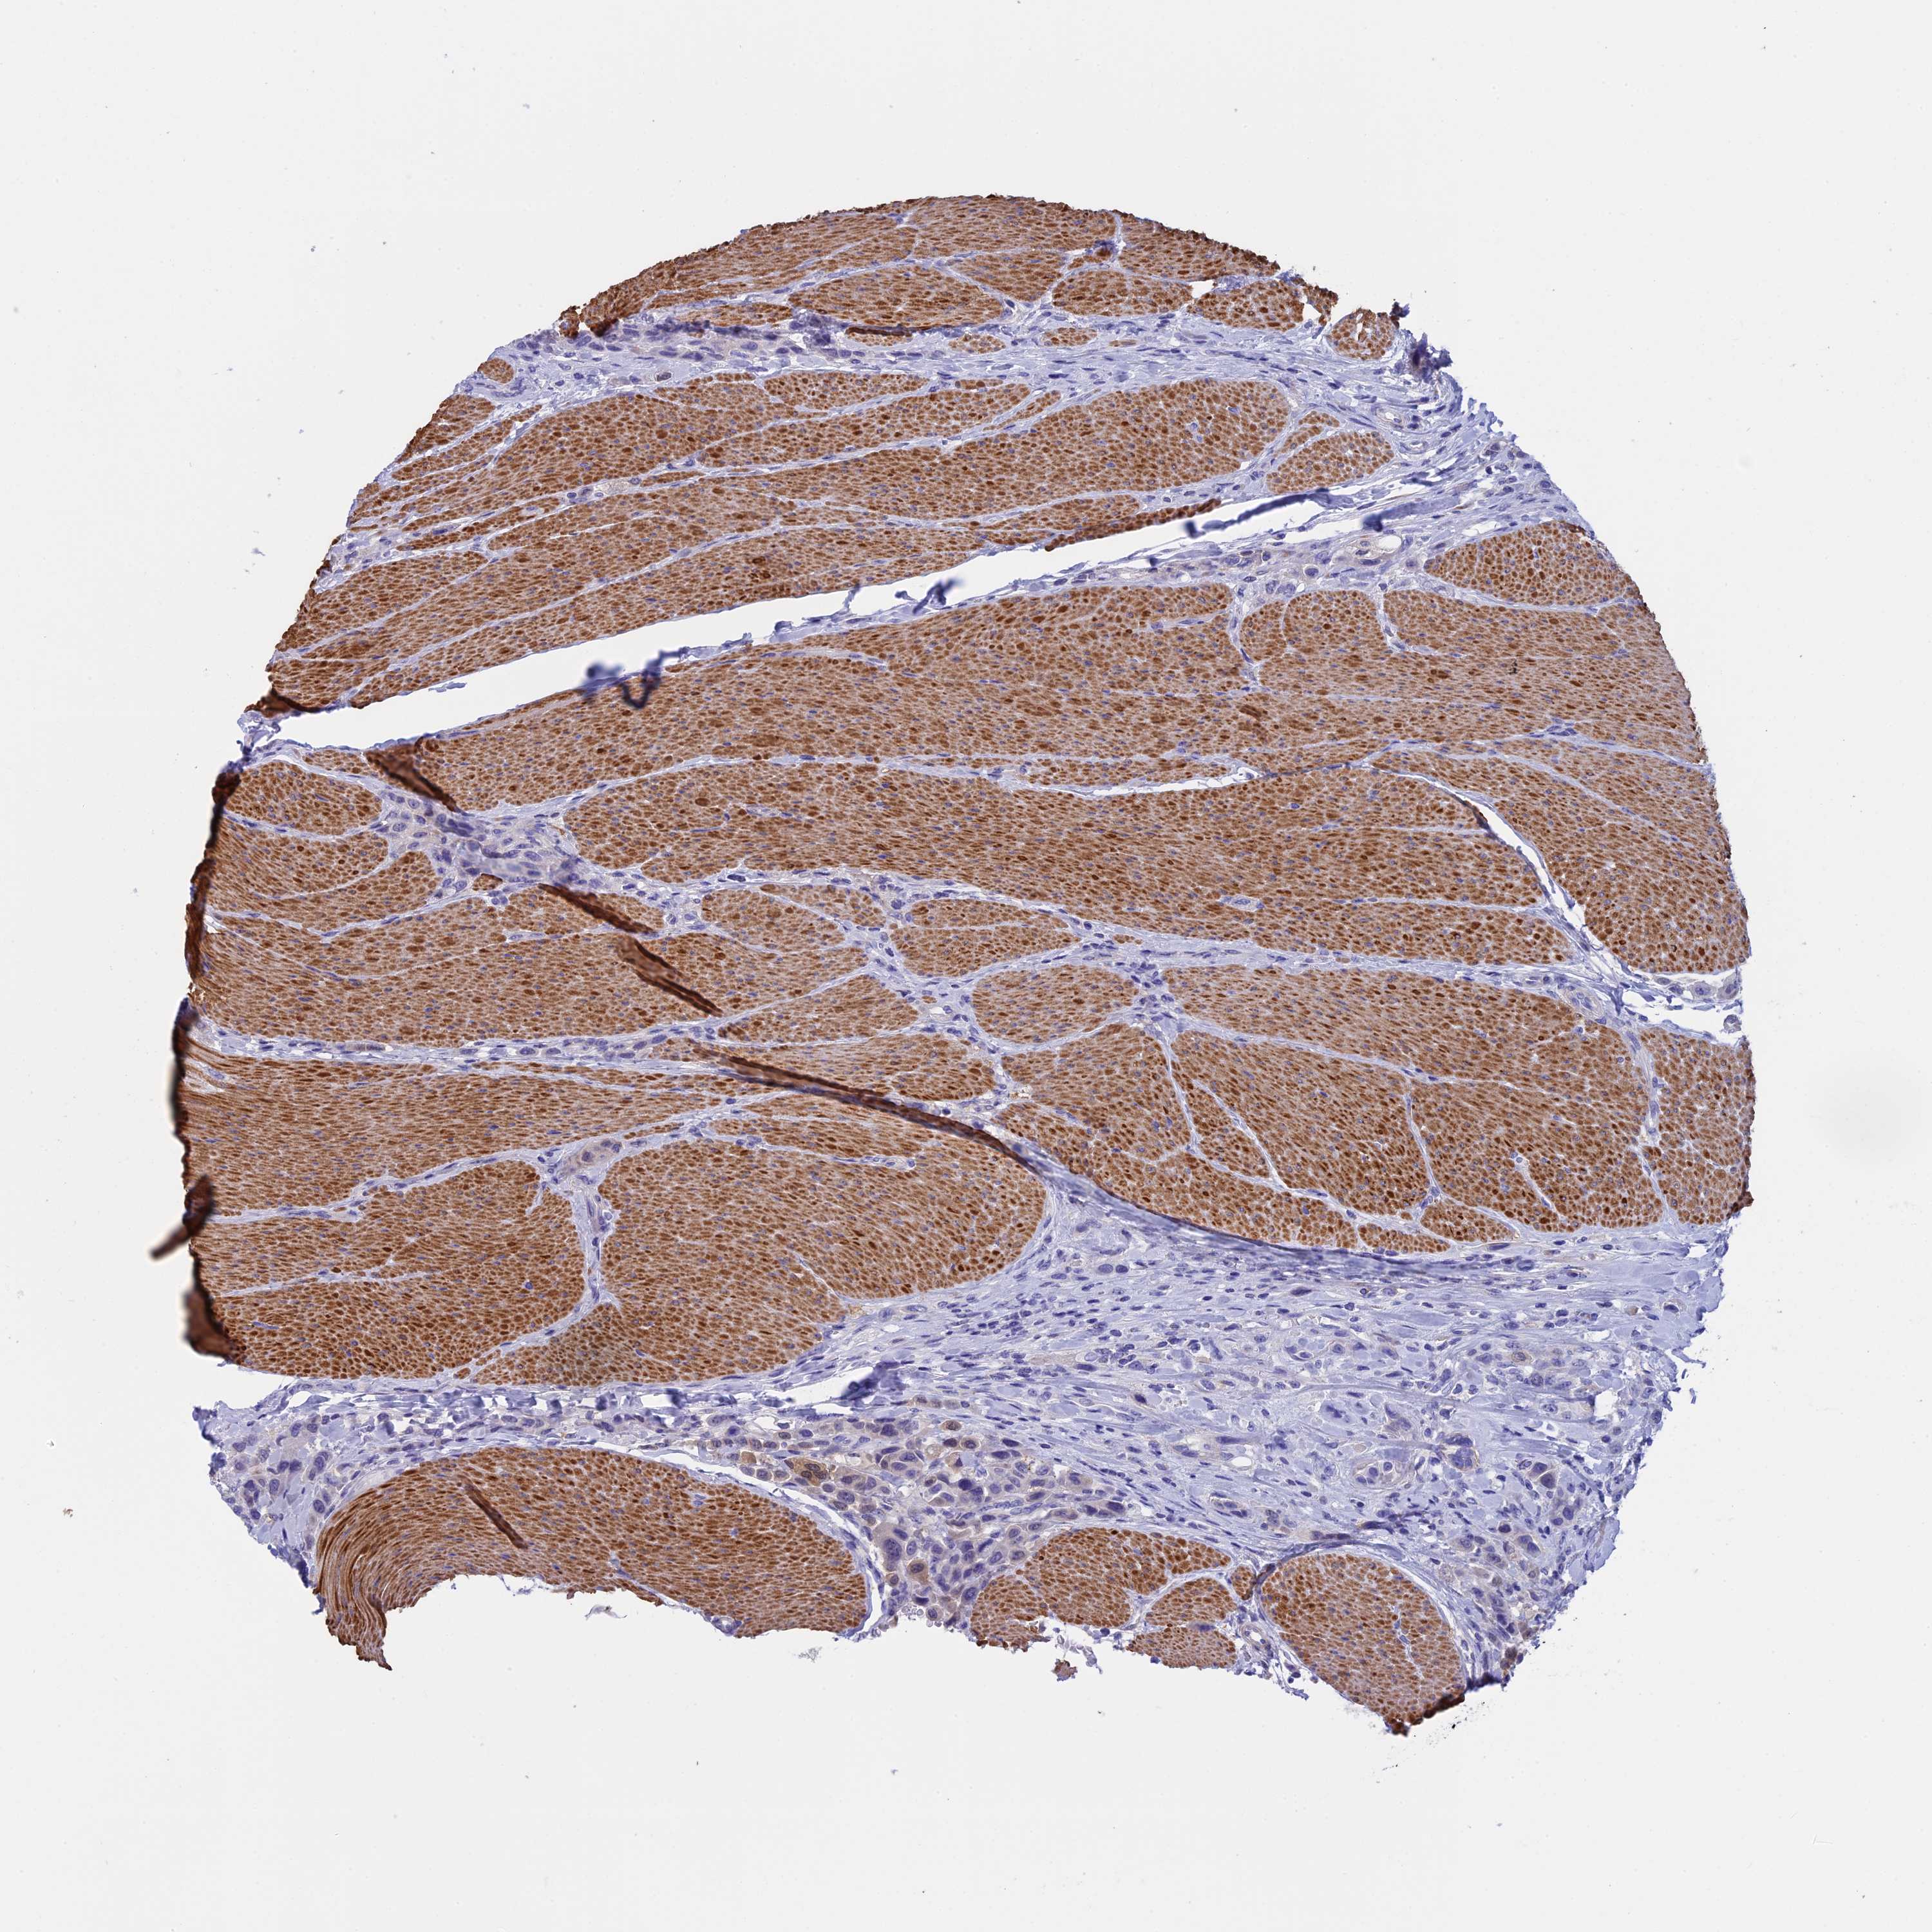

UROTHELIAL CANCER - Protein expressioni

A mouse-over function shows sample information and annotation data. Click on an image to view it in a full screen mode. Samples can be filtered based on level of antibody staining by selecting one or several of the following categories: high, medium, low and not detected. The assay and annotation is described here.

Note that samples used for immunohistochemistry by the Human Protein Atlas do not correspond to samples in the TCGA dataset.

Antibody stainingi

Antibody staining in the annotated cell types in the current human tissue is reported as not detected, low, medium, or high, based on conventional immunohistochemistry profiling in selected tissues. This score is based on the combination of the staining intensity and fraction of stained cells.

Each image is clickable and will lead to virtual microscopy that enables deeper exploration of all samples and also displays staining intensity scores, fraction scores and subcellular localization as well as patient and tissue information for each sample.

Antibody HPA039695

Staining

High

Medium

Low

Not detected

Intensity

Strong

Moderate

Weak

Negative

Quantity

>75%

75%-25%

<25%

None

Location

Nuclear

Cytoplasmic/membranous

Cytoplasmic/membranous,nuclear

Urothelial carcinoma, High grade

Urothelial carcinoma, Low grade